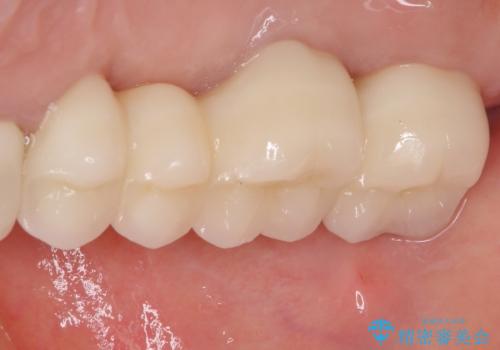

奥歯の歯槽骨が失われた 歯周外科処置後のセラミックブリッジ

処置後はオールセラミックブリッジにて補綴し、再発防止のために就寝時にナイトガード(マウスピース)を装着していただくこととしました。